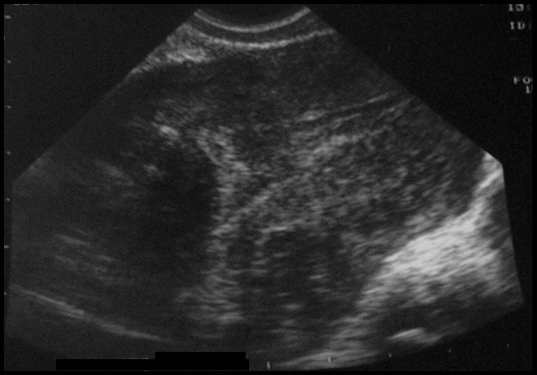

Myome sous-muqueux-intra-mural